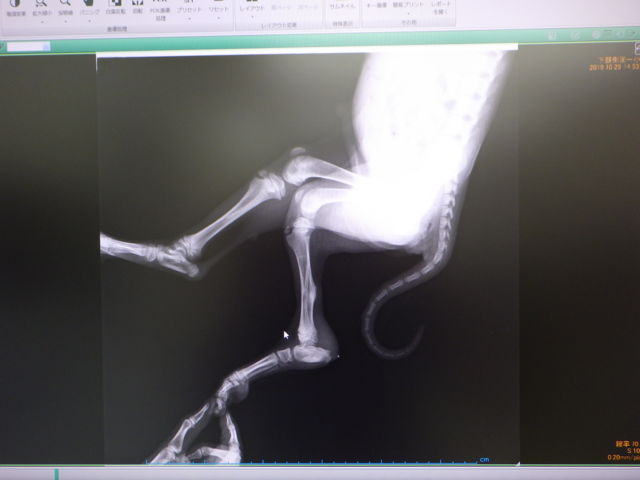

右後肢挙上(負重可能。伸展しにくいが屈伸可能)

→レントゲン検査:脛骨骨折、踵骨不形成

右踵骨の露出

右後ろ脚を骨折した跡があり、かかと部分の皮膚が剥けて骨が見えていますが、あまり痛がる様子もなく不自由ながらも足をついて歩いています

病院で診察してもらいましたが、骨折は自然治癒していて、骨の付き方は変ですが、これ以上の処置のしようは無くこのまま放置になります